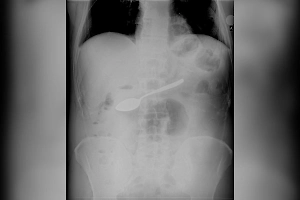

«Рана была загрязнена масляной смазкой от эскалатора, поэтому врачи сначала тщательно очистили рану, затем вправили вывих, сопоставили костные фрагменты и зафиксировали специальной спицей, которая была введена сквозь палец. После восстановили сухожилие разгибателя и кожные покровы», — отметили медики.

Операция длилась около трёх часов. Вскоре кровообращение в пальце было восстановлено. Пока что юная пациентка проходит реабилитацию в больнице, чтобы вернуть двигательную функцию.